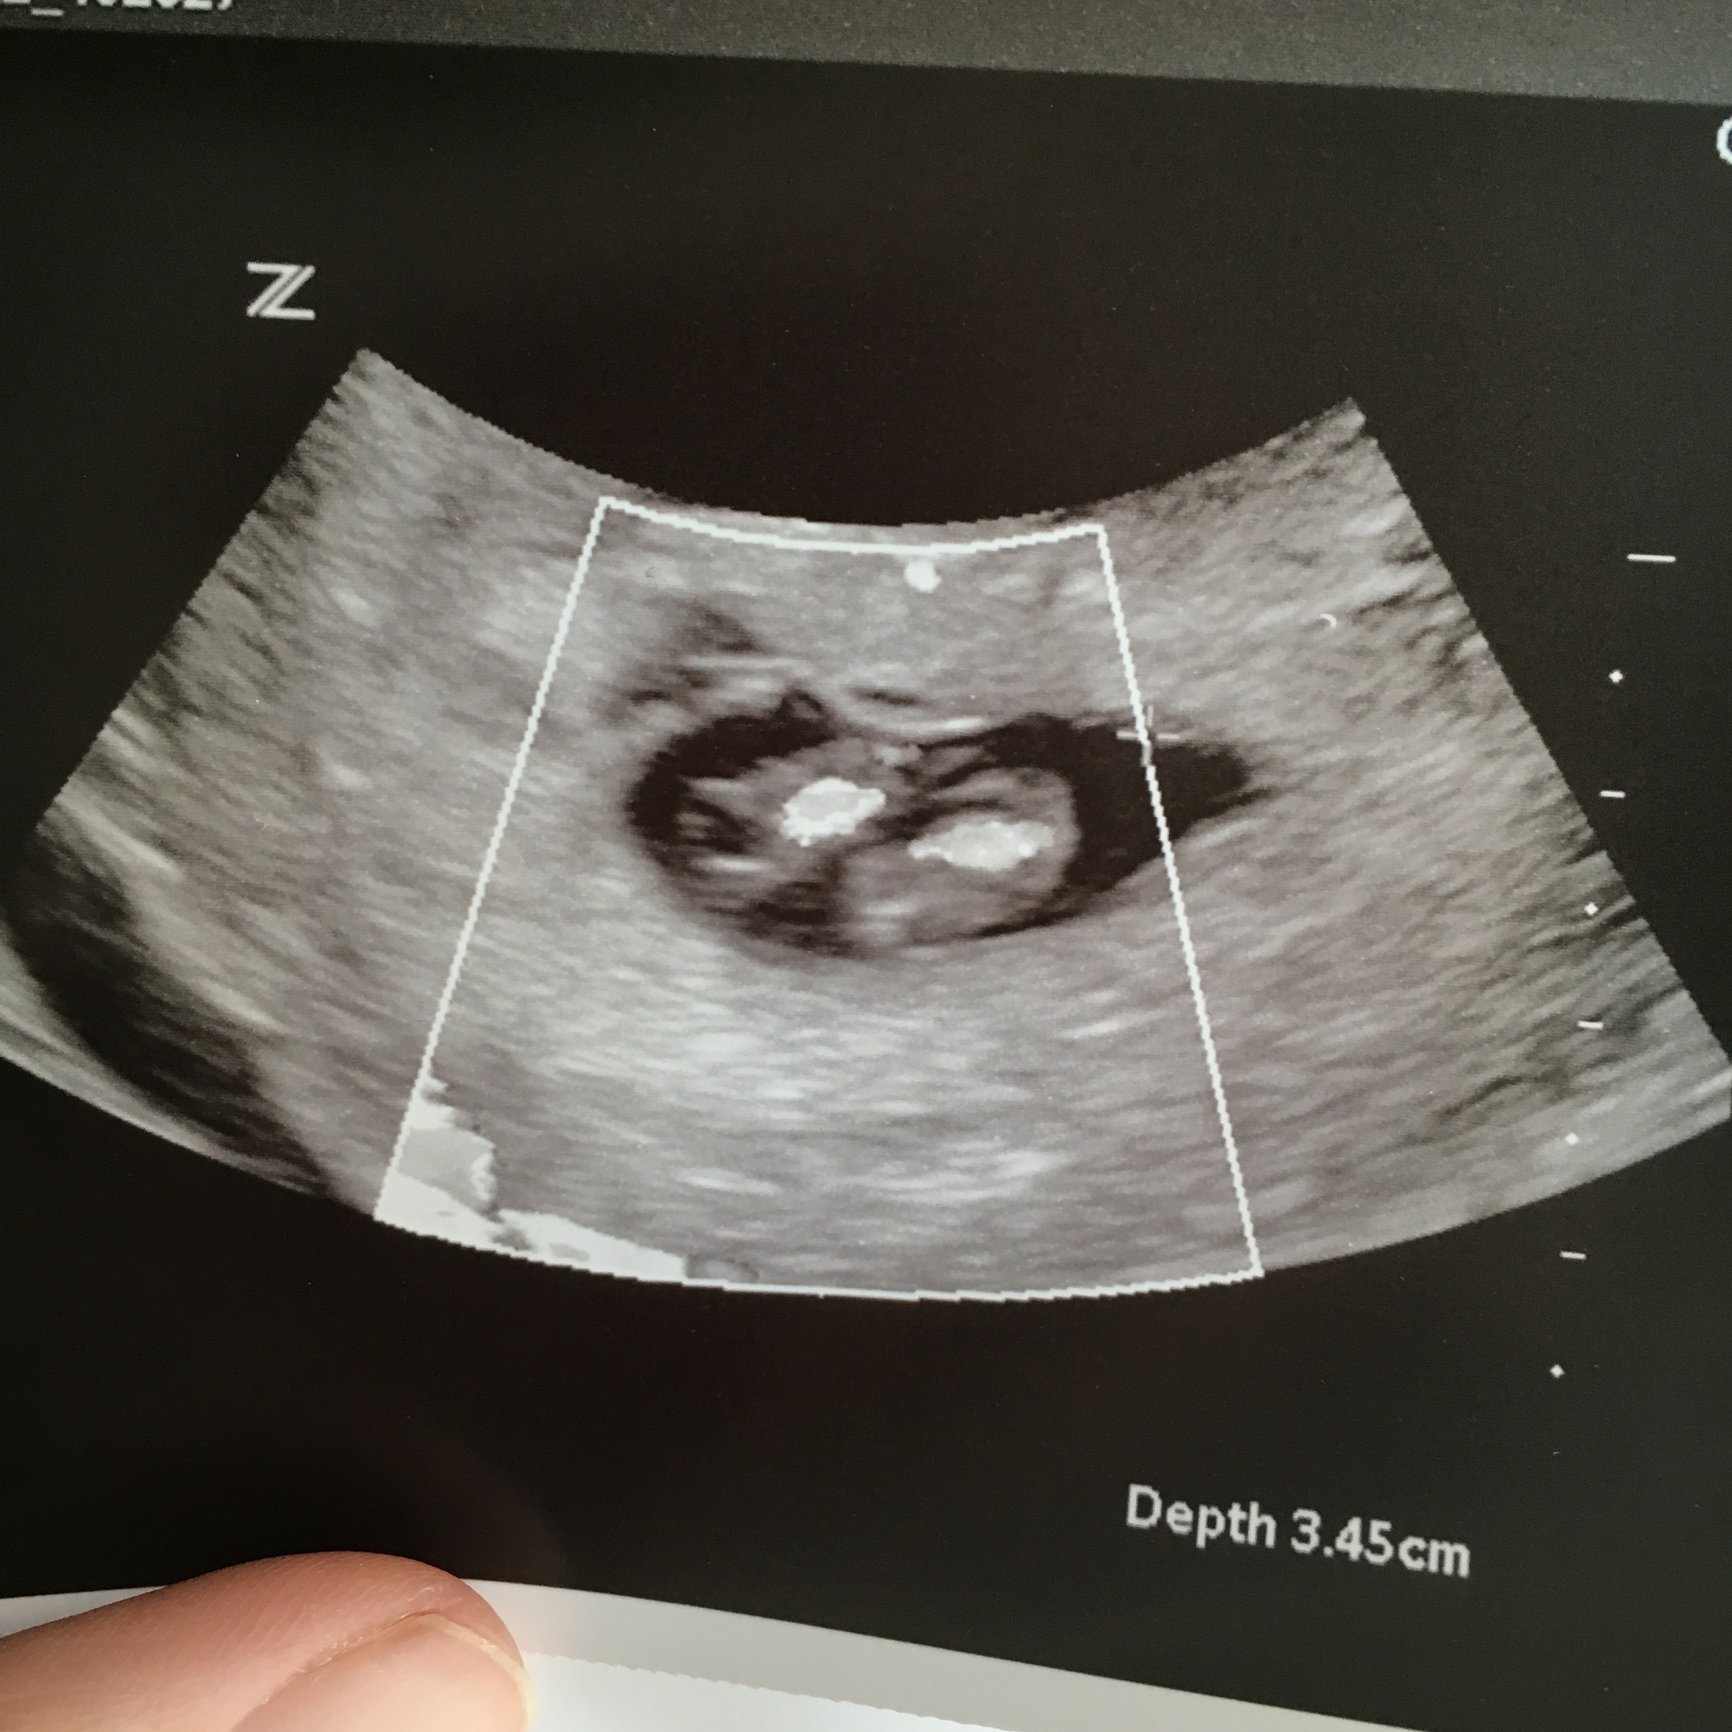

Had our first scan today!! 8w 4d measuring right on schedule saw little peanut wiggle on the screen and saw a heartbeat. They didn't tell us what the heart rate was though. Oh well there's always next time Best. Day. Ever!!

8w 4d measuring right on schedule

saw little peanut wiggle on the screen and saw a heartbeat. They didn't tell us what the heart rate was though. Oh well there's always next time

Best. Day. Ever!!